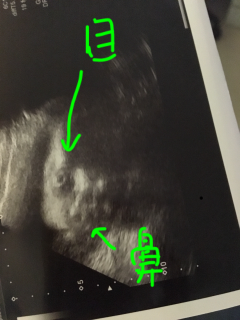

頭が少し大きめの直径7.7cm、体重が1458g順調で喜ばしいのだけど… 潰れて横に広がった鼻・分厚い唇がブサイクでとてもとてもショック。 女の子なのに人生ハードモードになるんじゃないか申し訳ない(涙) 先生が書いてくれたイラストがカワイイのがまた泣ける初めて書いてくれたけれど、赤ちゃんがあまりにブスで哀れに思ってくれたのだろうか あぁなんだか情緒不安定になる~! 2週間後は可愛く写ってくれますように。

どうしてこんな顔してるの(;;)笑 いつも夜中になると激しく動きます。 元気が一番です、、、